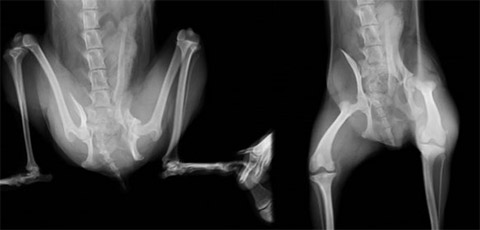

骨盤骨折

手術前:左腸骨体骨折および右仙腸関節脱臼が認められます。

手術後:プレートおよびラグスクリュー固定を行いました。